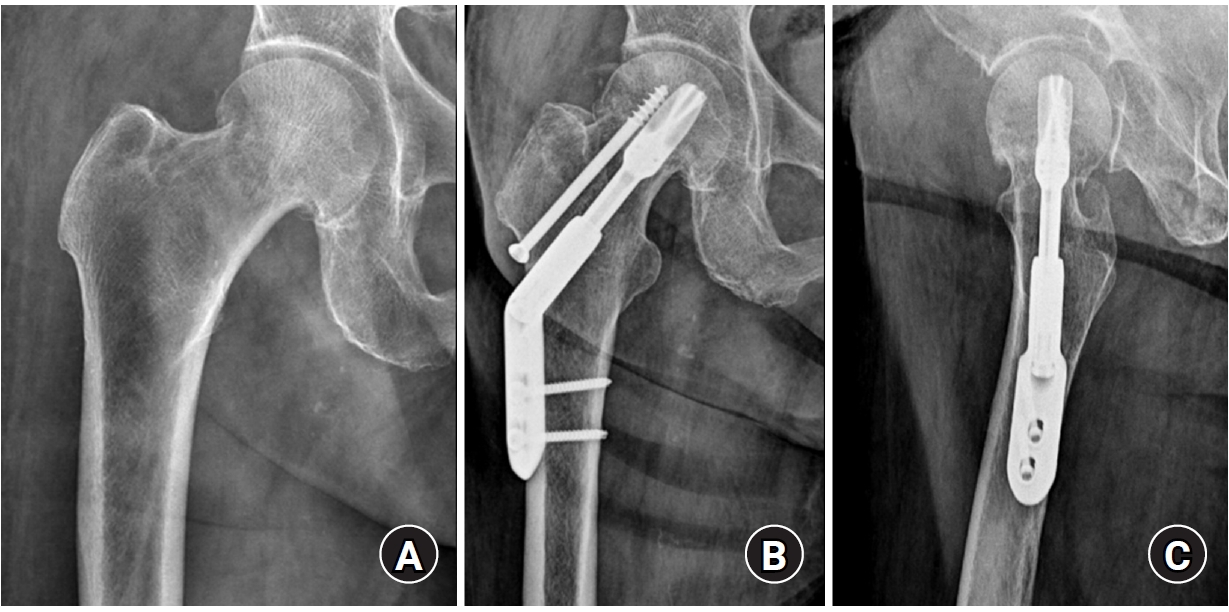

Standardized anteroposterior and lateral radiographs of the hip were obtained immediately postoperation and at each follow-up visit (6 weeks, 3 months, 6 months, 1 year, and annually thereafter). Radiological union was defined as the disappearance of the fracture line, accompanied by the absence of pain on full weight-bearing. Femoral neck shortening was calculated as the difference in the distance from the center of the femoral head to the lateral cortex of the femur between the immediate postoperative and final follow-up radiographs (Fig. 2). Femoral neck shortening was measured independently by two experienced orthopedic surgeons, and the average of their values was used for the analysis. Complications, including fixation failure (e.g., screw cut-out or excessive sliding), AVN of the femoral head, nonunion, and the need for revision surgery, were investigated.

Radiological outcomes

At the final follow-up, the union rate was 87.5% (21/24) in the FNS group and 95.8% (23/24) in the DHS group, with no statistically significant difference between the two groups (P=0.296) (Figs. 2, 3). The mean femoral neck shortening was measured at 6.1 mm in the FNS group and 5.9 mm in the DHS group, and no significant difference was observed (P=0.427).

Fig. 2.

(A, B) A 67-year-old female patient with a right femoral neck fracture (Garden type 1) treated with the femoral neck system. (C) The postoperative 4-year radiograph shows a well-healed fracture site and no complications related to the implant. Femoral neck shortening (D2‒D1) was calculated as the difference in the distance from the center of the femoral head to the lateral cortex of the femur between the immediate postoperative and final follow-up radiographs.

Fig. 2. (A, B) A 67-year-old female patient with a right femoral neck fracture (Garden type 1) treated with the femoral neck system. (C) The postoperative 4-year radiograph shows a well-healed fracture site and no complications related to the implant. Femoral neck shortening (D2‒D1) was calculated as the difference in the distance from the center of the femoral head to the lateral cortex of the femur between the immediate postoperative and final follow-up radiographs.